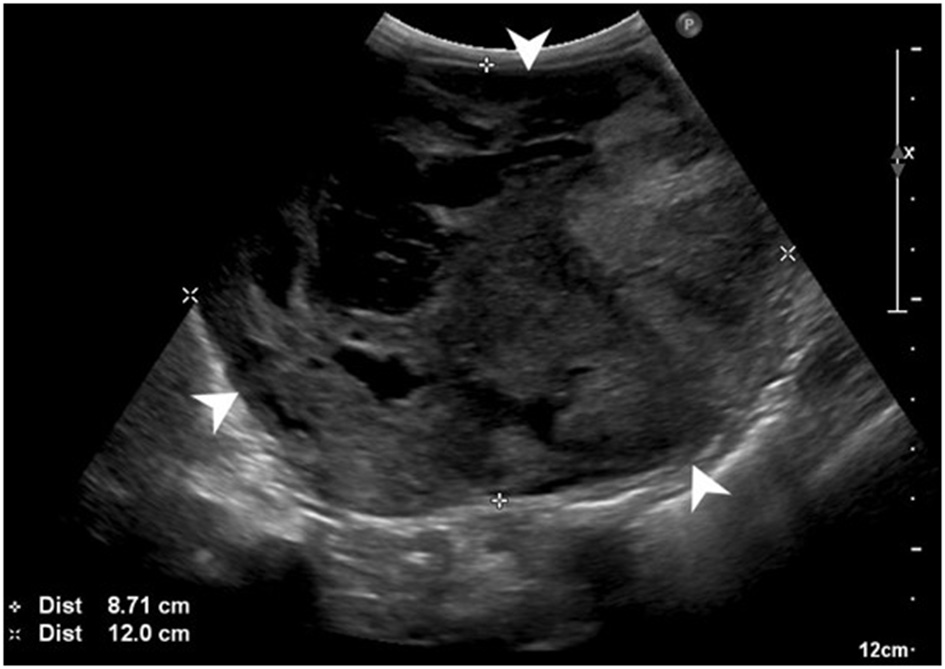

Abdominal ultrasonography showed a large (at least 8.7 × 12 cm), heterogeneous, cavitated mass extending cranially from the cranial pole of the left kidney and causing overall caudal displacement of the left kidney (Figure 1), as well as mild left renal lymphadenopathy (6.7 mm), diffuse peritoneal steatitis, and mild peritoneal effusion. Moderate bilateral degenerative renal changes with pyelectasia (left worse than right) were noted. No other significant abnormalities were detected. Thoracic radiographs revealed sternal lymphadenopathy, a bronchointerstitial pattern, caudal mediastinal widening, and multifocal disc space narrowing. There was no evidence of pulmonary metastatic disease.

Figure 1

Preoperative abdominal ultrasonographic study. Large, cavitated, heterogeneous mass (white arrowheads) arising from the left kidney.